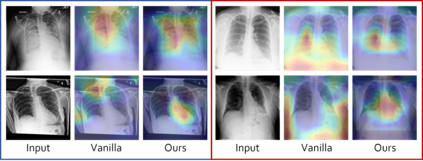

Deep learning models were frequently reported to learn from shortcuts like dataset biases. As deep learning is playing an increasingly important role in the modern healthcare system, it is of great need to combat shortcut learning in medical data as well as develop unbiased and trustworthy models. In this paper, we study the problem of developing debiased chest X-ray diagnosis models from the biased training data without knowing exactly the bias labels. We start with the observations that the imbalance of bias distribution is one of the key reasons causing shortcut learning, and the dataset biases are preferred by the model if they were easier to be learned than the intended features. Based on these observations, we proposed a novel algorithm, pseudo bias-balanced learning, which first captures and predicts per-sample bias labels via generalized cross entropy loss and then trains a debiased model using pseudo bias labels and bias-balanced softmax function. We constructed several chest X-ray datasets with various dataset bias situations and demonstrated with extensive experiments that our proposed method achieved consistent improvements over other state-of-the-art approaches.